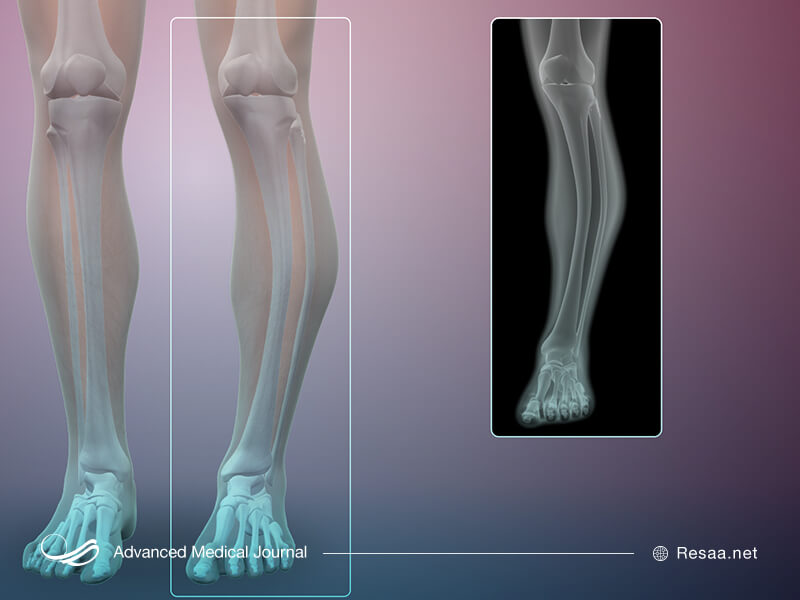

استخوانهایی که بیشترین آسیبپذیری را دارند:

- استخوان ران

- استخوانهای ساق

- لگن

- ستون فقرات

- جمجمه

اگر استخوان شما به روشی نادرست تغییر یافته باشد، پزشک ممکن است بتواند بیماری شما را از نظر علائم و معاینه جسمی تشخیص دهد اما معمولاً برای تأیید آن به پرتو نگاری و آزمایش خون احتیاج دارید. حتی اگر علائم واضحی نداشته باشید، برخی نتایج آزمایشهای خون به بیماری پاژه اشاره میکنند.

بعضی اوقات پزشک، اسکن استخوان ایزوتوپ “isotope” که مؤثرترین روش برای مشخص کردن محل قرارگیری استخوان تحت تأثیر بیماری است را تجویز میکند، تا متوجه شود چه مقدار از استخوانها تحت تأثیر قرار گرفته و چقدر فعال است. یک دوز کوچک و قابل تحمل ایزوتوپ رادیواکتیو (جهت تشخیص بیماری در اسکن استخوان) به رگ شما تزریق میشود و چند ساعت بعد، کل اسکلت شما اسکن میگردد. میزان کمی رادیواکتیو تزریق میگردد تا به بدن شما آسیب نرساند. ایزوتوپ در نواحی استخوانی متاثر از بیماری پاژه متمرکز میشود به طوری که با یک دوربین مخصوص، هنگام اسکن از بدن به طور واضح ظاهر میگردد. ماده رادیواکتیو، پس از اسکن و از طریق ادرار، به سرعت از بدن شما خارج میشود.